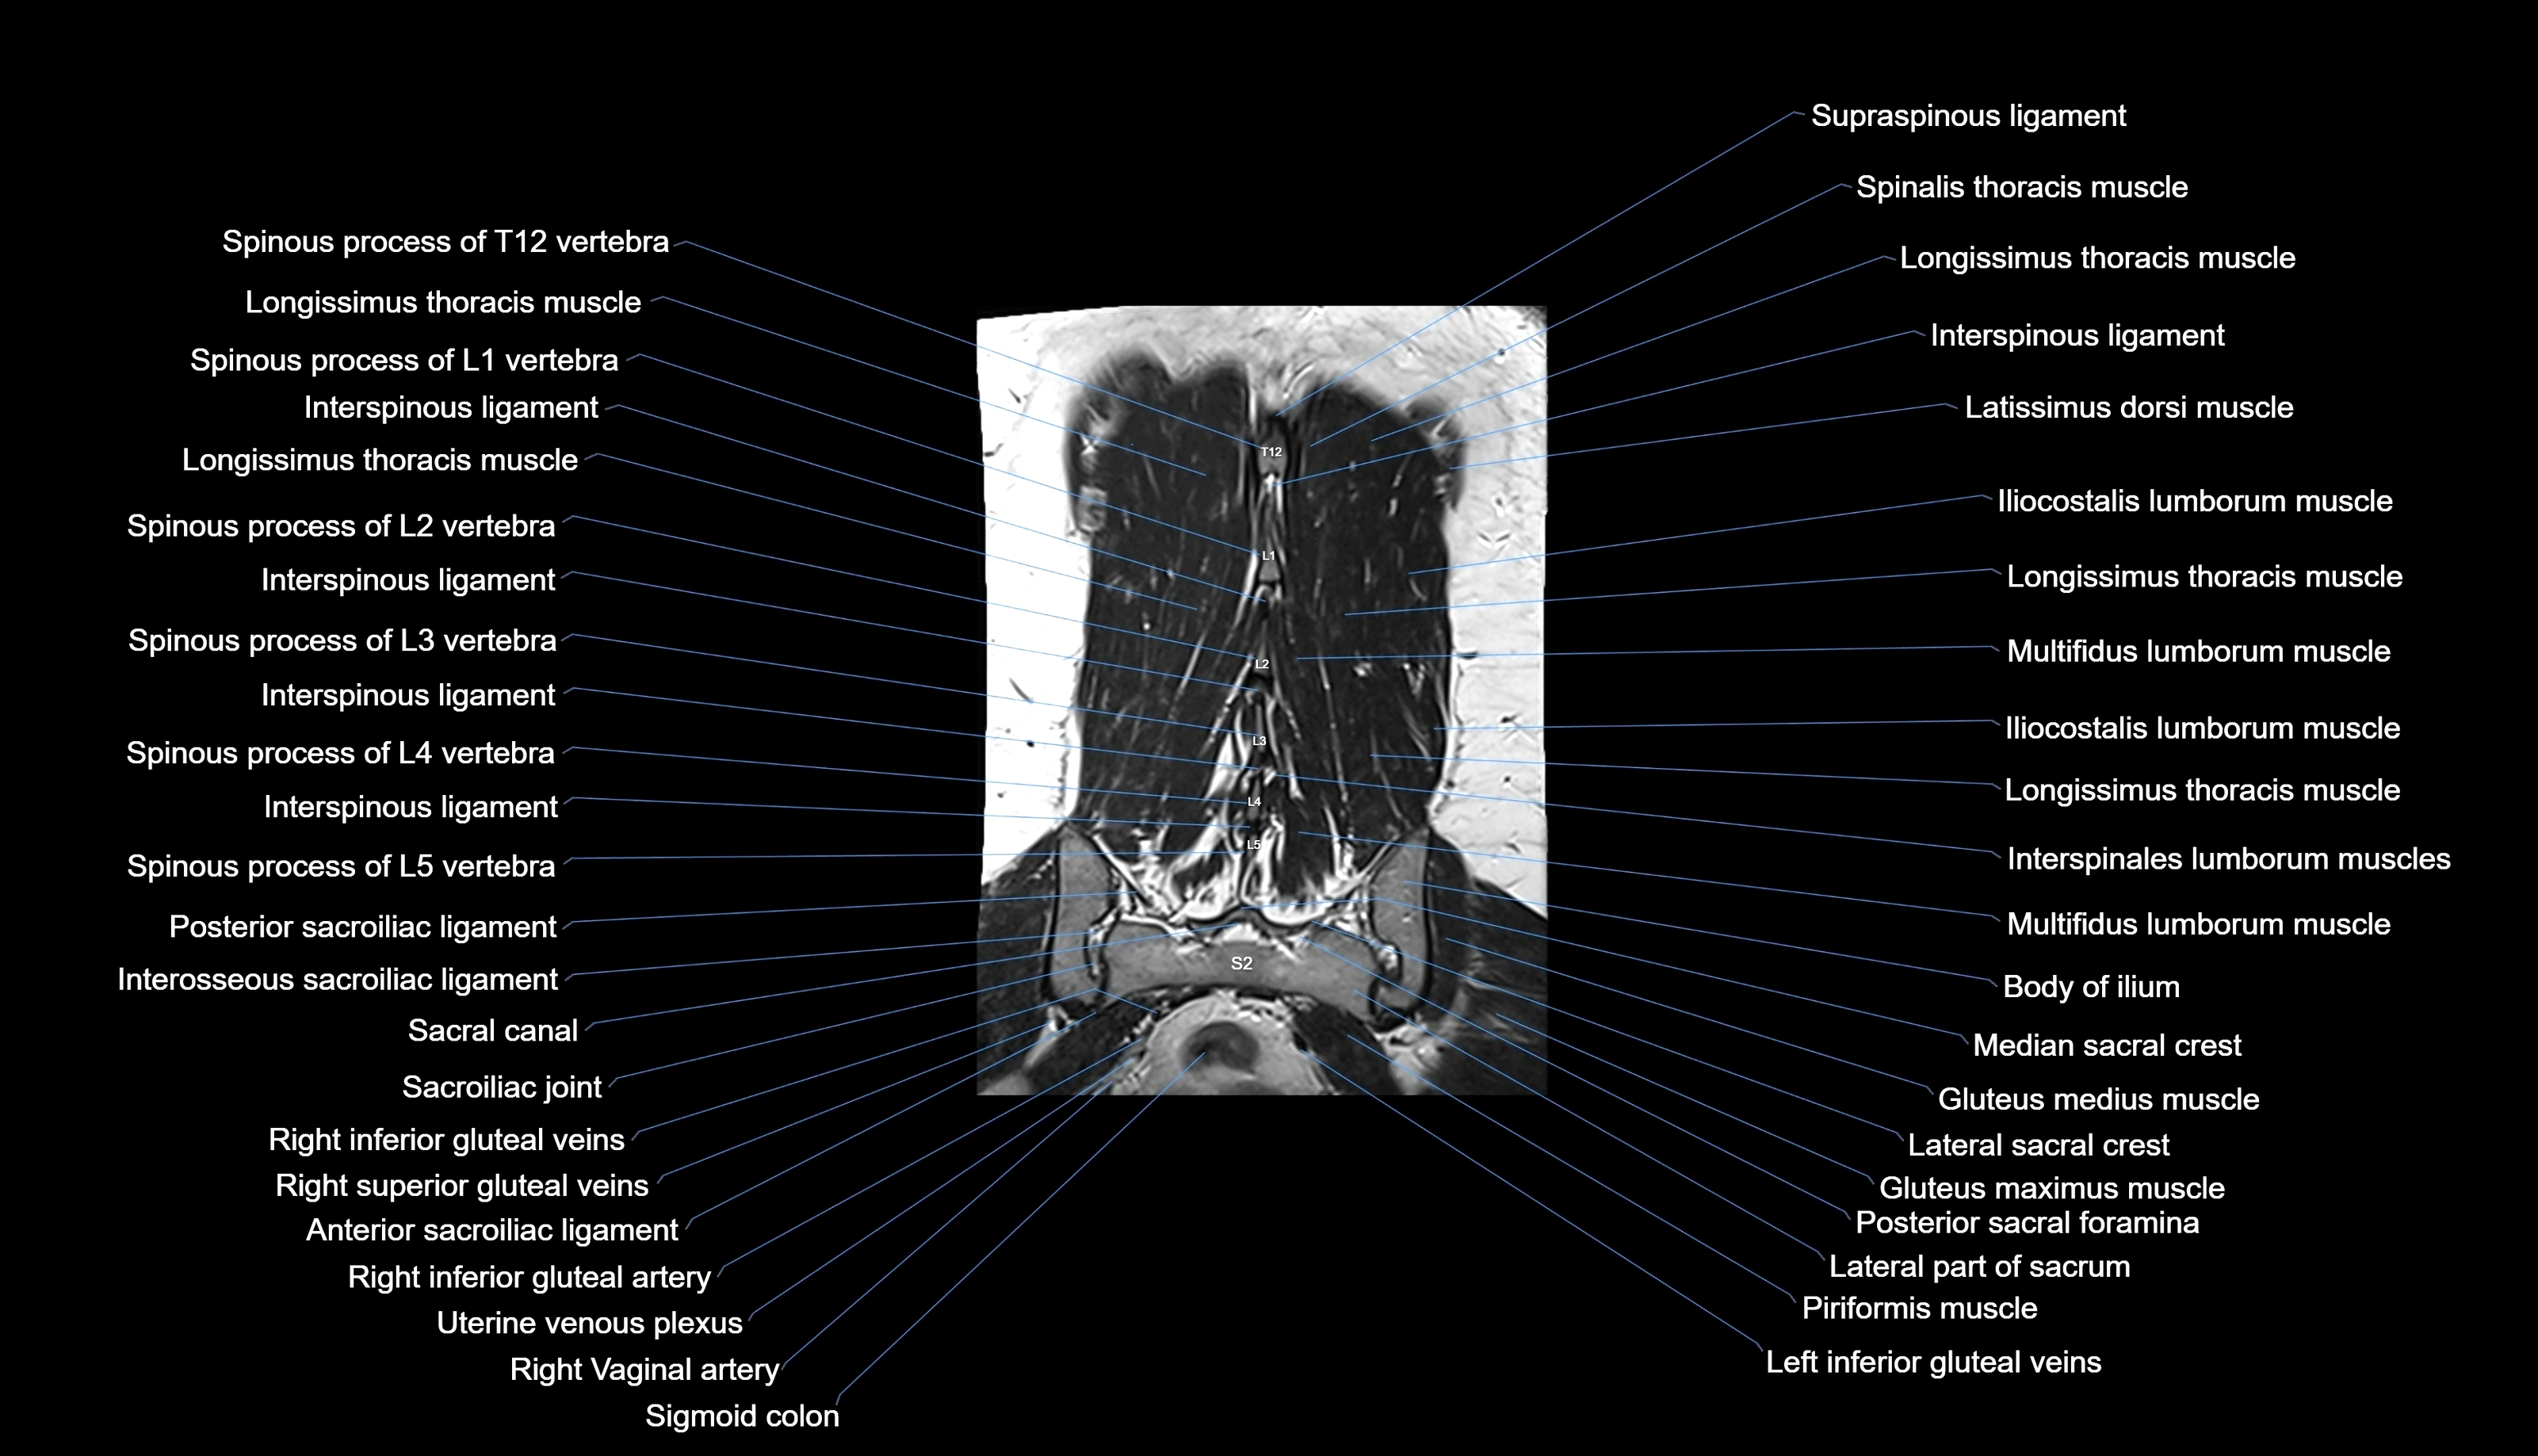

MRI images